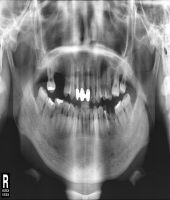

| ● 진료과목 : [임플란트] 치주환자의 임플란트 보철치료

| ● 내용 : 50대 치주환자의 임플란트치료. |